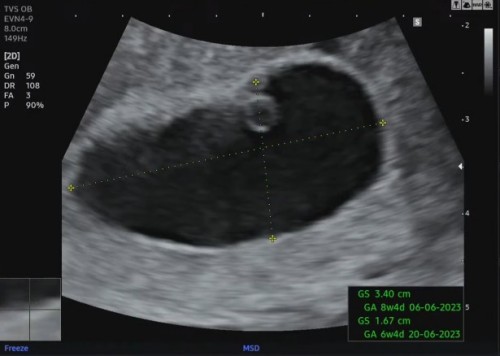

ตั้งครรภ์8wนับจากประจำเดือนล่าสุด ยังไม่เจอตัวอ่อนเจอแต่ถุงไข่แดง หมอบอกว่าท้องลม100%

ตั้งครรภ์8wนับจากประจำเดือนล่าสุด ยังไม่เจอตัวอ่อนเจอแต่ถุงไข่แดง ค่าhcg 50000+หมอบอกว่าท้องลม100% แบบนี้ยังมีหวังจะเจอน้องอีกไหมคะ รบกวนแม่ๆที่มีประสบการณ์ช่วยแนะนำหน่อยค่ะตอนนี้กังวลมากเลย หมอนัดซาวด์อีก10วันค่ะ